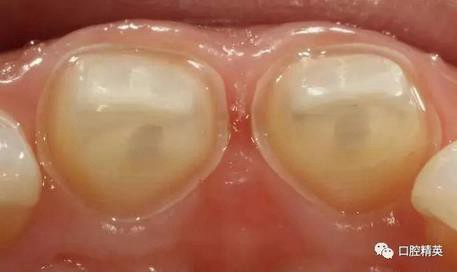

術(shù)前檢查

可見兩側(cè)齦緣外形不平整

齲洞低已近髓